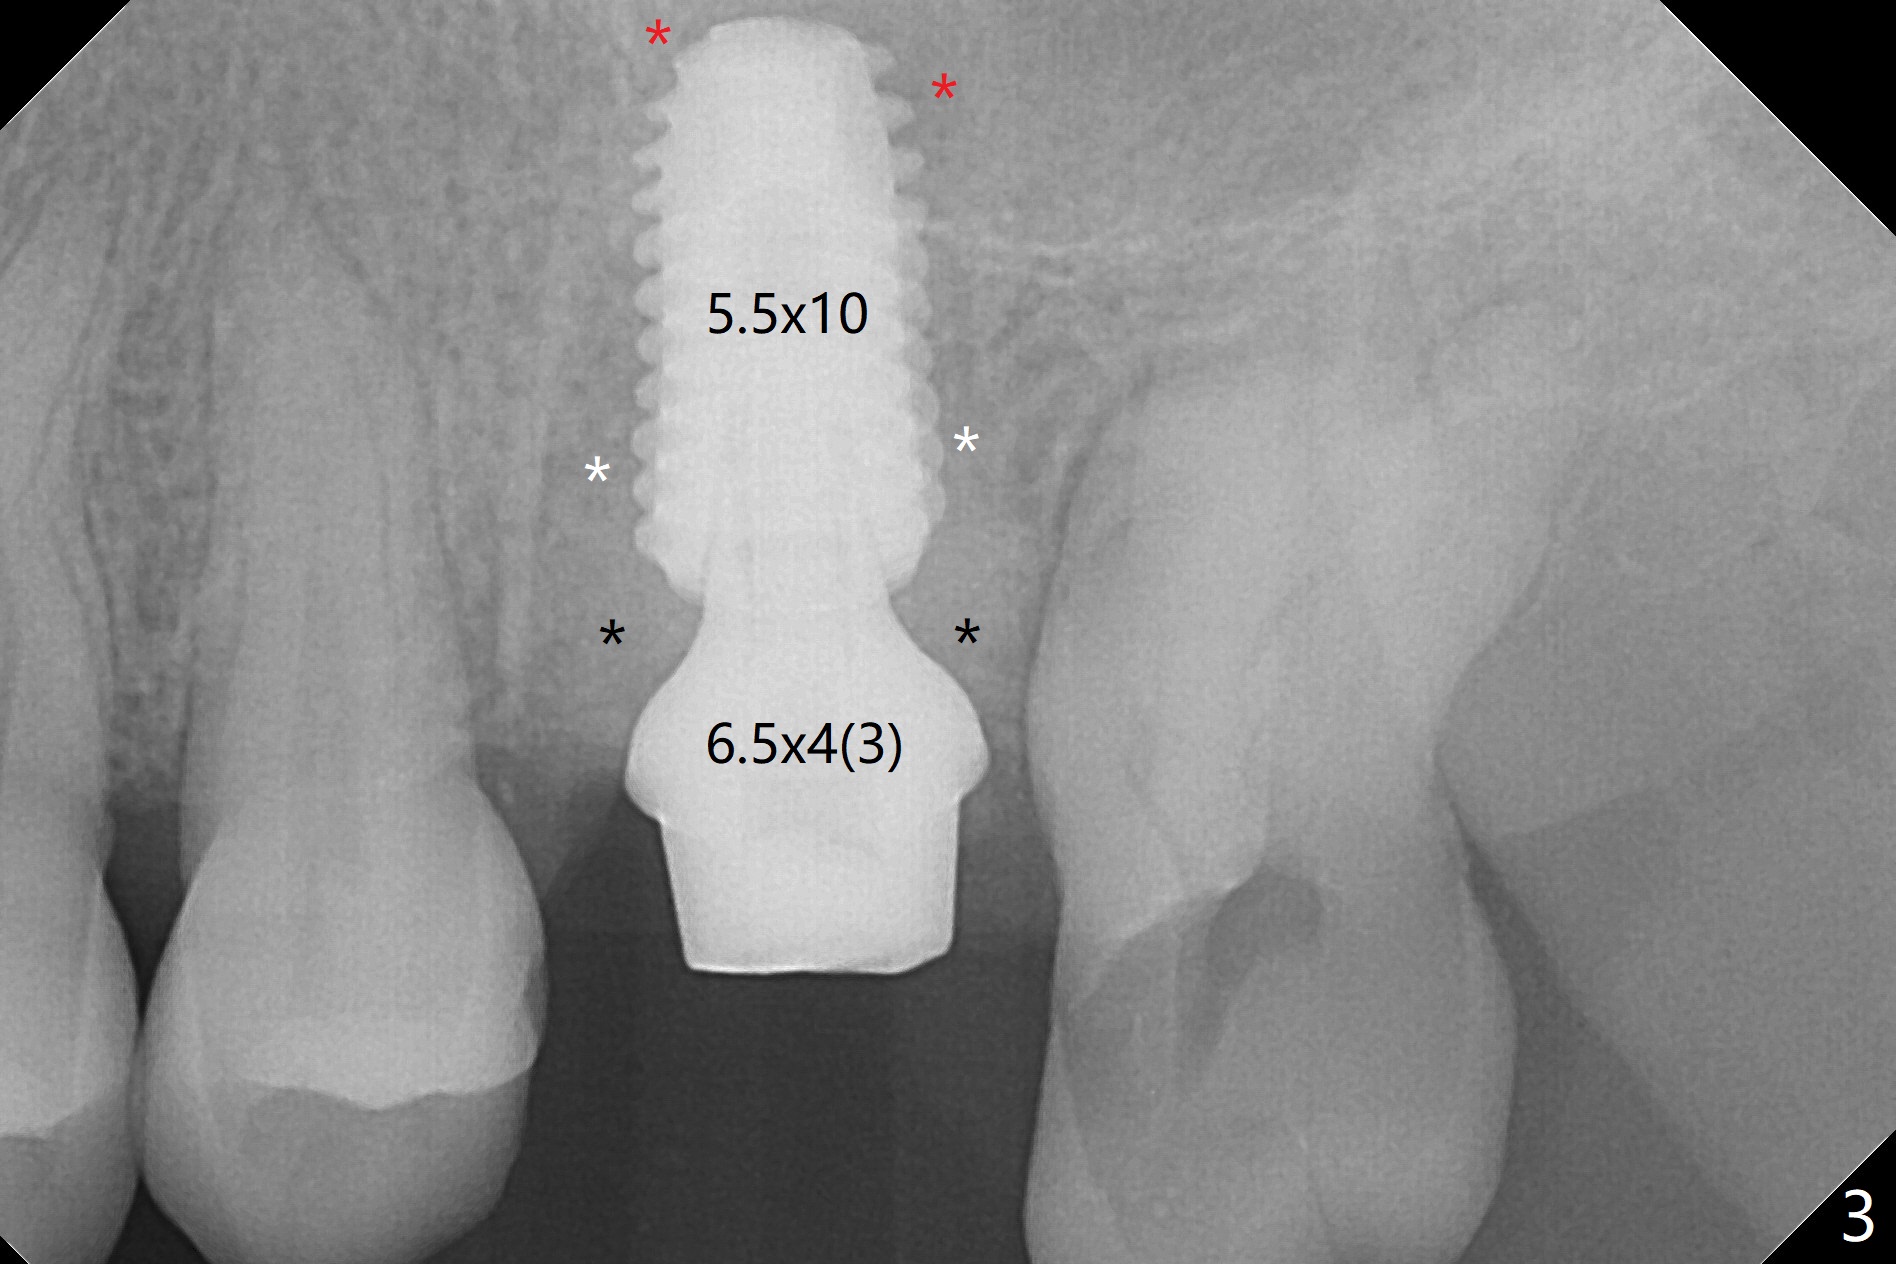

After removal of granulation tissue from the sockets associated with the fractured tooth at #14 (Fig.1 (* granulation tissue)) and initial osteotomy in the septum with a 2 mm drill for 8.5 mm, the sinus floor is penetrated by a parallel pin (Fig.2). But the sinus membrane remains intact until osteotomy finishes with a 4.8 mm drill. Following sinus lift with Vera Graft with autogenous bone (Fig.3 red *), a 5.5x10 mm implant is placed ~ 1 mm coronal to the septal crest and 1-3 mm apical to the surrounding crest (mesiodisto-buccopalatal, >55 Ncm). After further bone graft around the implant (Fig.3 white *), a 6.5x4(3) mm abutment is inserted with the 3rd round of grafting (Fig.3,4 black *). An immediate provisional is fabricated to keep the allograft in place. The implant seems to have osteointegrated 5 months postop (Fig.5).